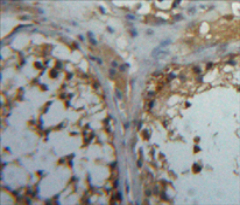

IHC (Immunohistochemistry)

(Paraformaldehyde-fixed, paraffin embedded (human liver); Antigen retrieval by boiling in sodium citrate buffer (pH6.0) for 15min; Block endogenous peroxidase by 3% hydrogen peroxide for 20 minutes; Blocking buffer (normal goat serum) at 37 degree C for 30min; Antibody incubation with (Kindlin) Polyclonal Antibody, Unconjugated (bs-17063R) at 1:200 overnight at 4 degree C, followed by operating according to SP Kit(Rabbit) (sp-0023) instructionsand DAB staining.)